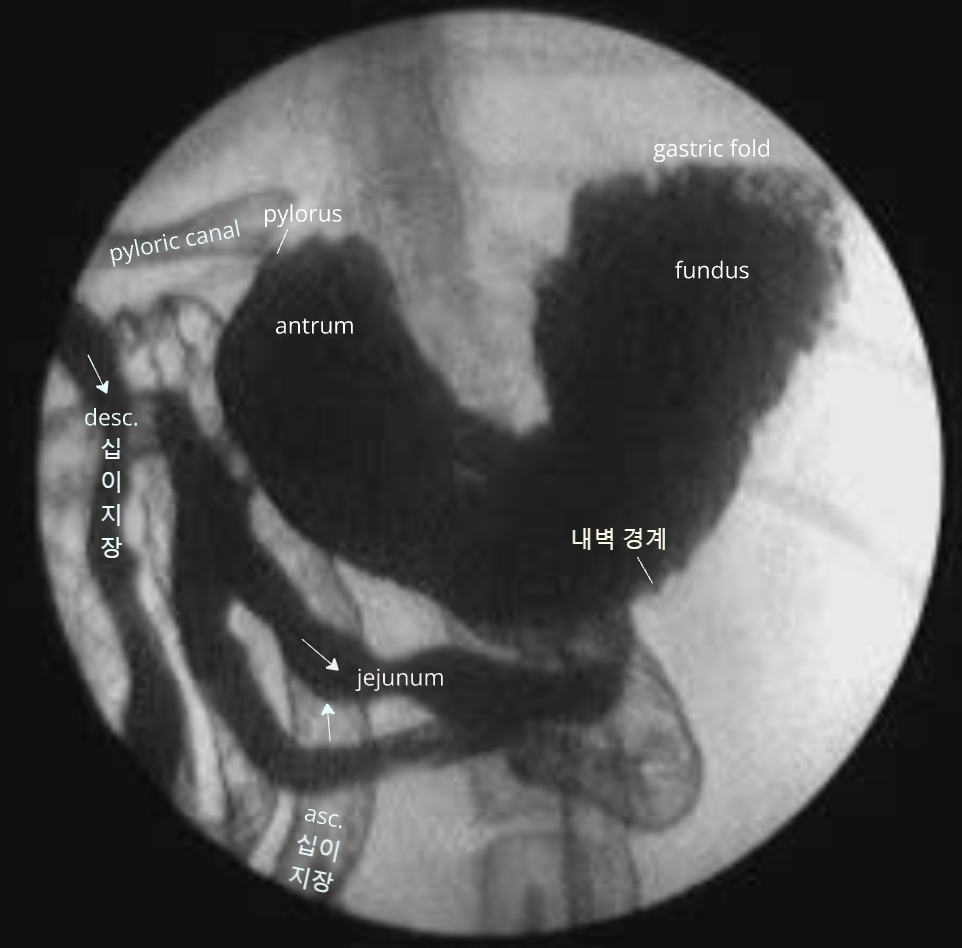

- GI tract contrast technique : ์กฐ์์ ๋ฅผ ํฌ์ฌํ๋ฉด ์๊ฐ๋๋ณ๋ก ์ง์ฅ๊น์ง ํ๋ฌ๋ด๋ ค๊ฐ. ์ฌ๋ฌ ์ฐจ๋ก ์ดฌ์ํ์ฌ ๋ฃจํธ ์ถ์ ๊ฐ๋ฅ.

์ ์ ๊ตฌ์กฐ ๊ด์ฐฐ

์์ ๋ณ์ ์๊ฒฌ

์๋ด ์ด๋ฌผ

์ด๋ฌผ์ ์ข ๋ฅ์ ๋ฐ๋ผ ๋ฐฉ์ฌ์ ํฌ๊ณผ์ฑ์ด ๋ค์ํ ์ ๋๋ก ๋ํ๋จ, ์์ธ์ ๋ฐฉํฅ์ ๋ฐ๋ผ ๋ชจ์๋ ๋ค์ํ๊ฒ ์ดฌ์๋จ.

X-ray ์ด์ ์ ์ด์ง์ด ์ค์ (๋ฐฐ ๊ทผ์ฒ์์ ๋ง์ ธ์ง ์ ์์)

์ด๋ฌผ์ ์ด์ํ์์์ shadowing ๋ฐ์, ์์ฆ์ X-ray๋ณด๋ค ์ด์ํ๊ฐ ์ฐ์ ๋๊ธฐ๋ ํจ.

- ์์ ๊ธ์ฌ โ ์ ์์ธ์์ ์ด์ํ ๊ฒ์ฌ โ shadowing์ ๋ณด์ด๋ ์ด๋ฌผ์ ์ฆ๊ฑฐ ํ์ธ

์กฐ์์ ๋ ๊ฐ์์ 1์๊ฐ 20๋ถ~2์๊ฐ, ๊ณ ์์ด์์ 1์๊ฐ ๋ด๋ก ๋ค ๋ฐฐ์ถ๋จ.

- ์ด๋ณด๋ค ์ค๋ ๊ฑธ๋ฆฌ๋ฉด ์์ ๋ฐฐ์ถ์ ๋ฌธ์ ๊ฐ ์๋ ๊ฒ. (๋ฐฐ์ถํ๋ ํ์ด ์ฝํด์ง, ํต๋ก๊ฐ ๋งํ, ์กฐ์์ ํก์ฐฉ/ํก์ ์ด๋ฌผ ์กด์ฌ)